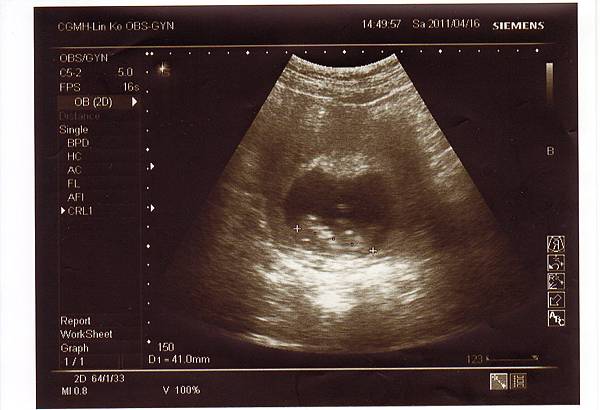

2011.04.16 第一次正式產檢,寶寶很乖地長大,當天我被抽了五管血,

做最基本的檢查